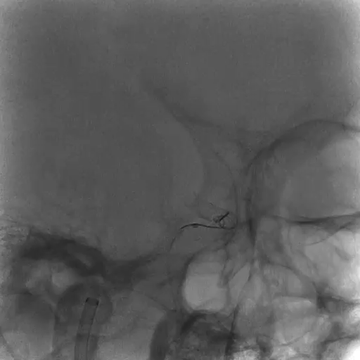

Tubridge Plus Case 5